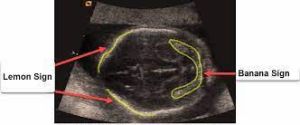

• Often visualizes two cranial abnormalities assoc. w/ hydrocephalus & Chiari II malformations:

• Lemon sign: scalloping of frontal bones on biparietal view, present in 80% of fetuses w/ myelomeningocele

• Banana sign: abnormal midbrain shape, elongated cerebellum, & obliteration of the cisterna magna, present in 93% of myelomeningocele fetuses; false-positive rate only 0.88%

• Both signs highly diagnostic of myelomeningocele, even when spinal abnormality not directly visualized